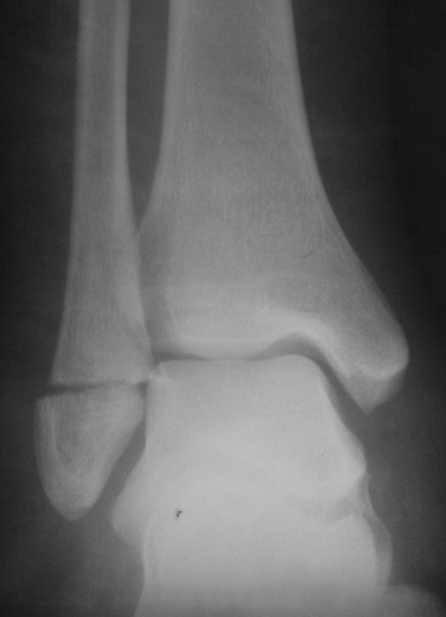

Перелом латеральной лодыжки.

На одном из форумов заспорили о тактике. Женщина 23 года, рост 158, вес 55, профессия: менеджер, хобби: верховая езда, горные лыжи, велосипеды, не курит, сопутствующих заболеваний нет. 28 июня упала с лошади. первый рентген:

Иммобилизация гипсовым сапожком до 20 августа На сегодня- Гипс снаят, со слов больной "Наступать на ногу не больно, но страшно. Сустав и мышцы, конечно, плохо работают."

Есть ортез.

Что делать?

1. Оперировать.

2. Не оперировать.